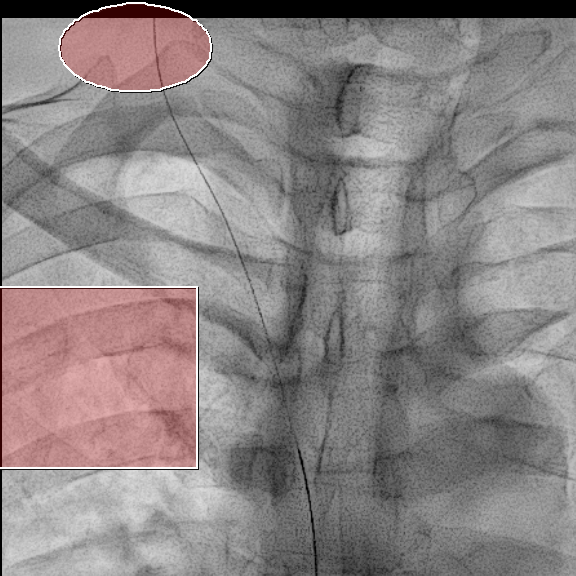

X-ray 를 보면서 이 와이어가 적절한 위치로 가는지 잘 봐야합니다.

대부분의 경우는 상대정맥으로 잘 내려가지만 내려가는 경로 상 기정맥(Azygos vein)이나 내흉정맥(Internal thoracic vein)이 있을 수도 있거든요.

이런 정맥들로 잘못 들어가게 되면 정맥포트가 금방 기능을 잃어버립니다.